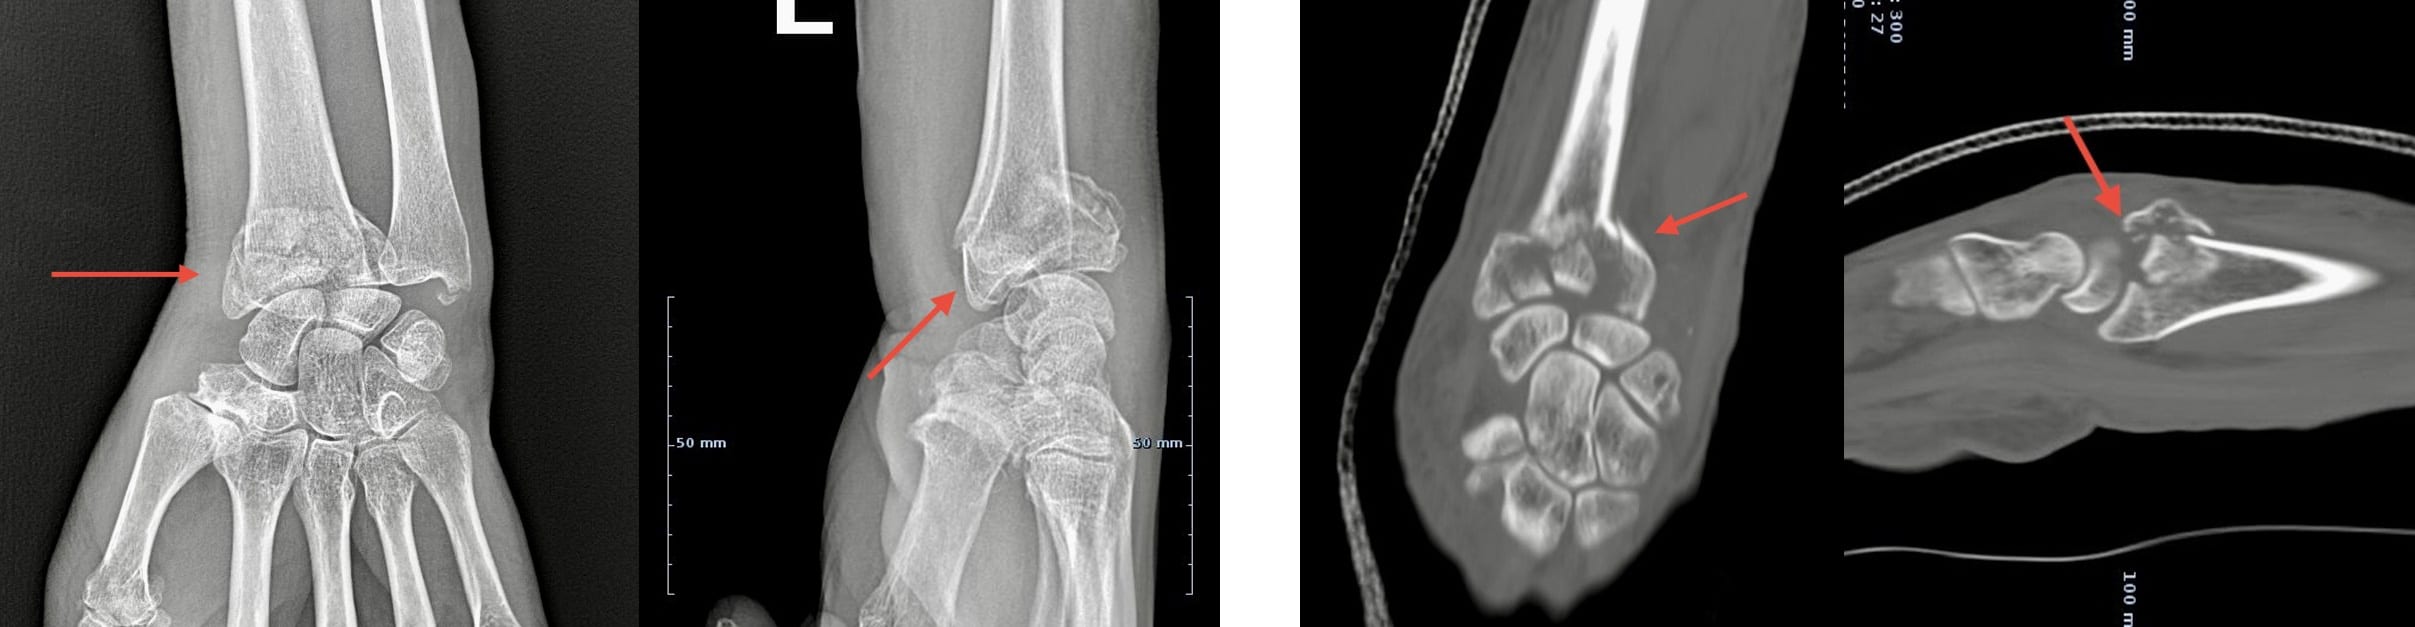

Raio-X e TAC de uma fractura multifragmentar complexa do rádio distal, com afundamento da superfície articular

Raio-X (esquerda) e TAC (direita) de uma fractura multifragmentar complexa do rádio distal, com afundamento da superfície articular

Raio-x simples são a base da avaliação das fracturas distais do rádio.

Frequentemente, para melhor caracterização das fracturas, é necessário fazer uma TAC, que geralmente revela em detalhe a posição dos fragmentos ósseos.